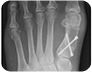

当院の整形外科では、特に関節や骨に対しての治療を専門分野の専門医が担当して行っております。 骨切り術・人工関節置換・各種固定術・脊柱管形成術・椎間板ヘルニア手術・リハビリにも力を入れており、早期退院・早期社会復帰が可能となるよう努力しております。 椎間板ヘルニアに関して、患者さんに合わせた様々な手術方法を選択しております。従来法よりも早期に退院可能なレーザー治療も行っておりますので、ぜひ外来受診時にご相談ください。